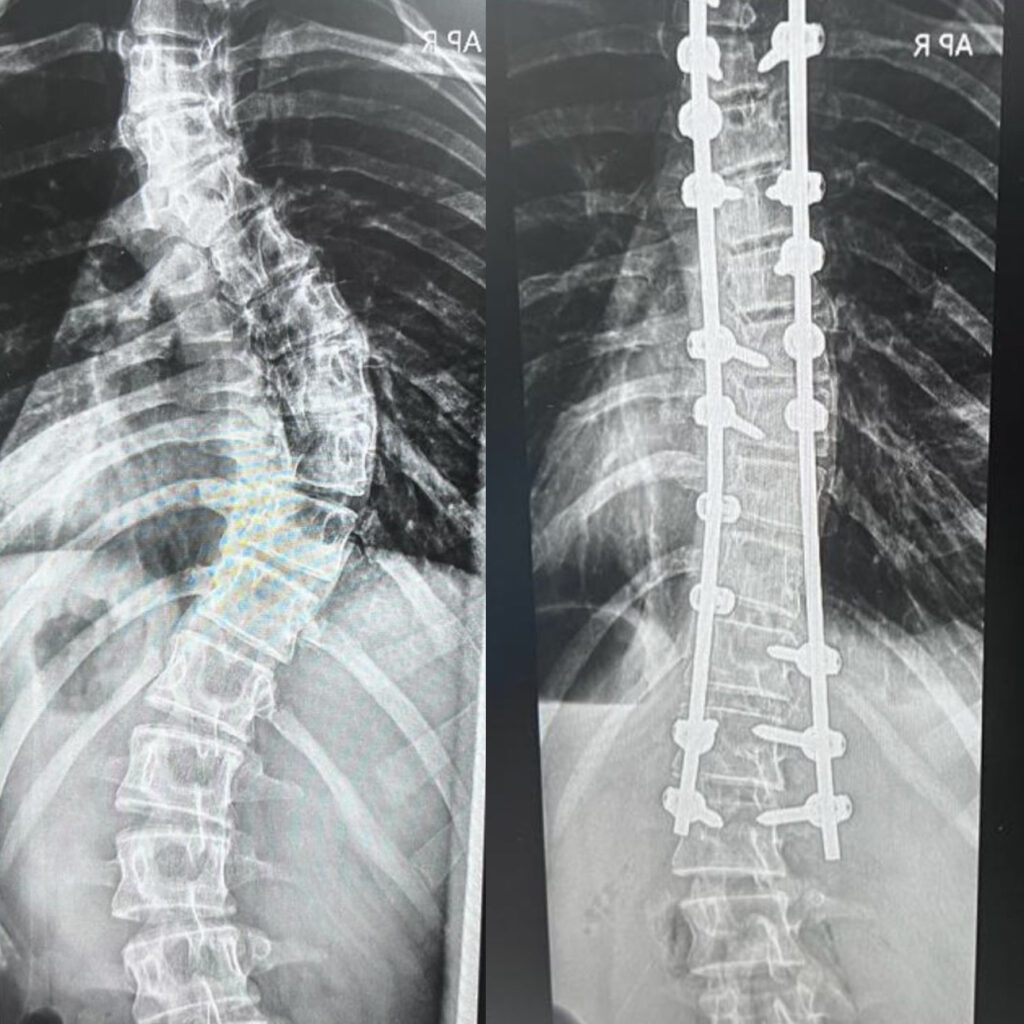

Physiotherapy was what helped me get through bracing and relieved my pain which started getting worse and more intense as months went by. At the time it felt as though I would never get better but the support I had from my family got me through it. Fast forward to 2023 where I had my usual x-ray checkup, and this was when things took a turn for the worse. I had severe scoliosis where my top curve measured 73 degrees and the other curve 33 degrees. I was left with no other choice than to undergo spinal fusion surgery. I was 15 years old and felt scared and nervous for the 6 weeks that was yet to come. Despite what I thought, I made it through it. Although it was the toughest thing that I had ever been through, after 6 hours of surgery, I did it. It was a rollercoaster of emotions and definitely tested my limits but, 2 rods and 19 screws later, I did it. I’m currently 17 years old, 2025, and I embrace my scar with pride, a testament of my strength and determination. What I thought was the worst thing to happen, turned out to be the best life lesson. I no longer take things for granted and I am grateful that I get to share my story in hopes of making others feel seen and loved, there is a community that is here for you. Scoliosis does not define you; it only makes you stronger.